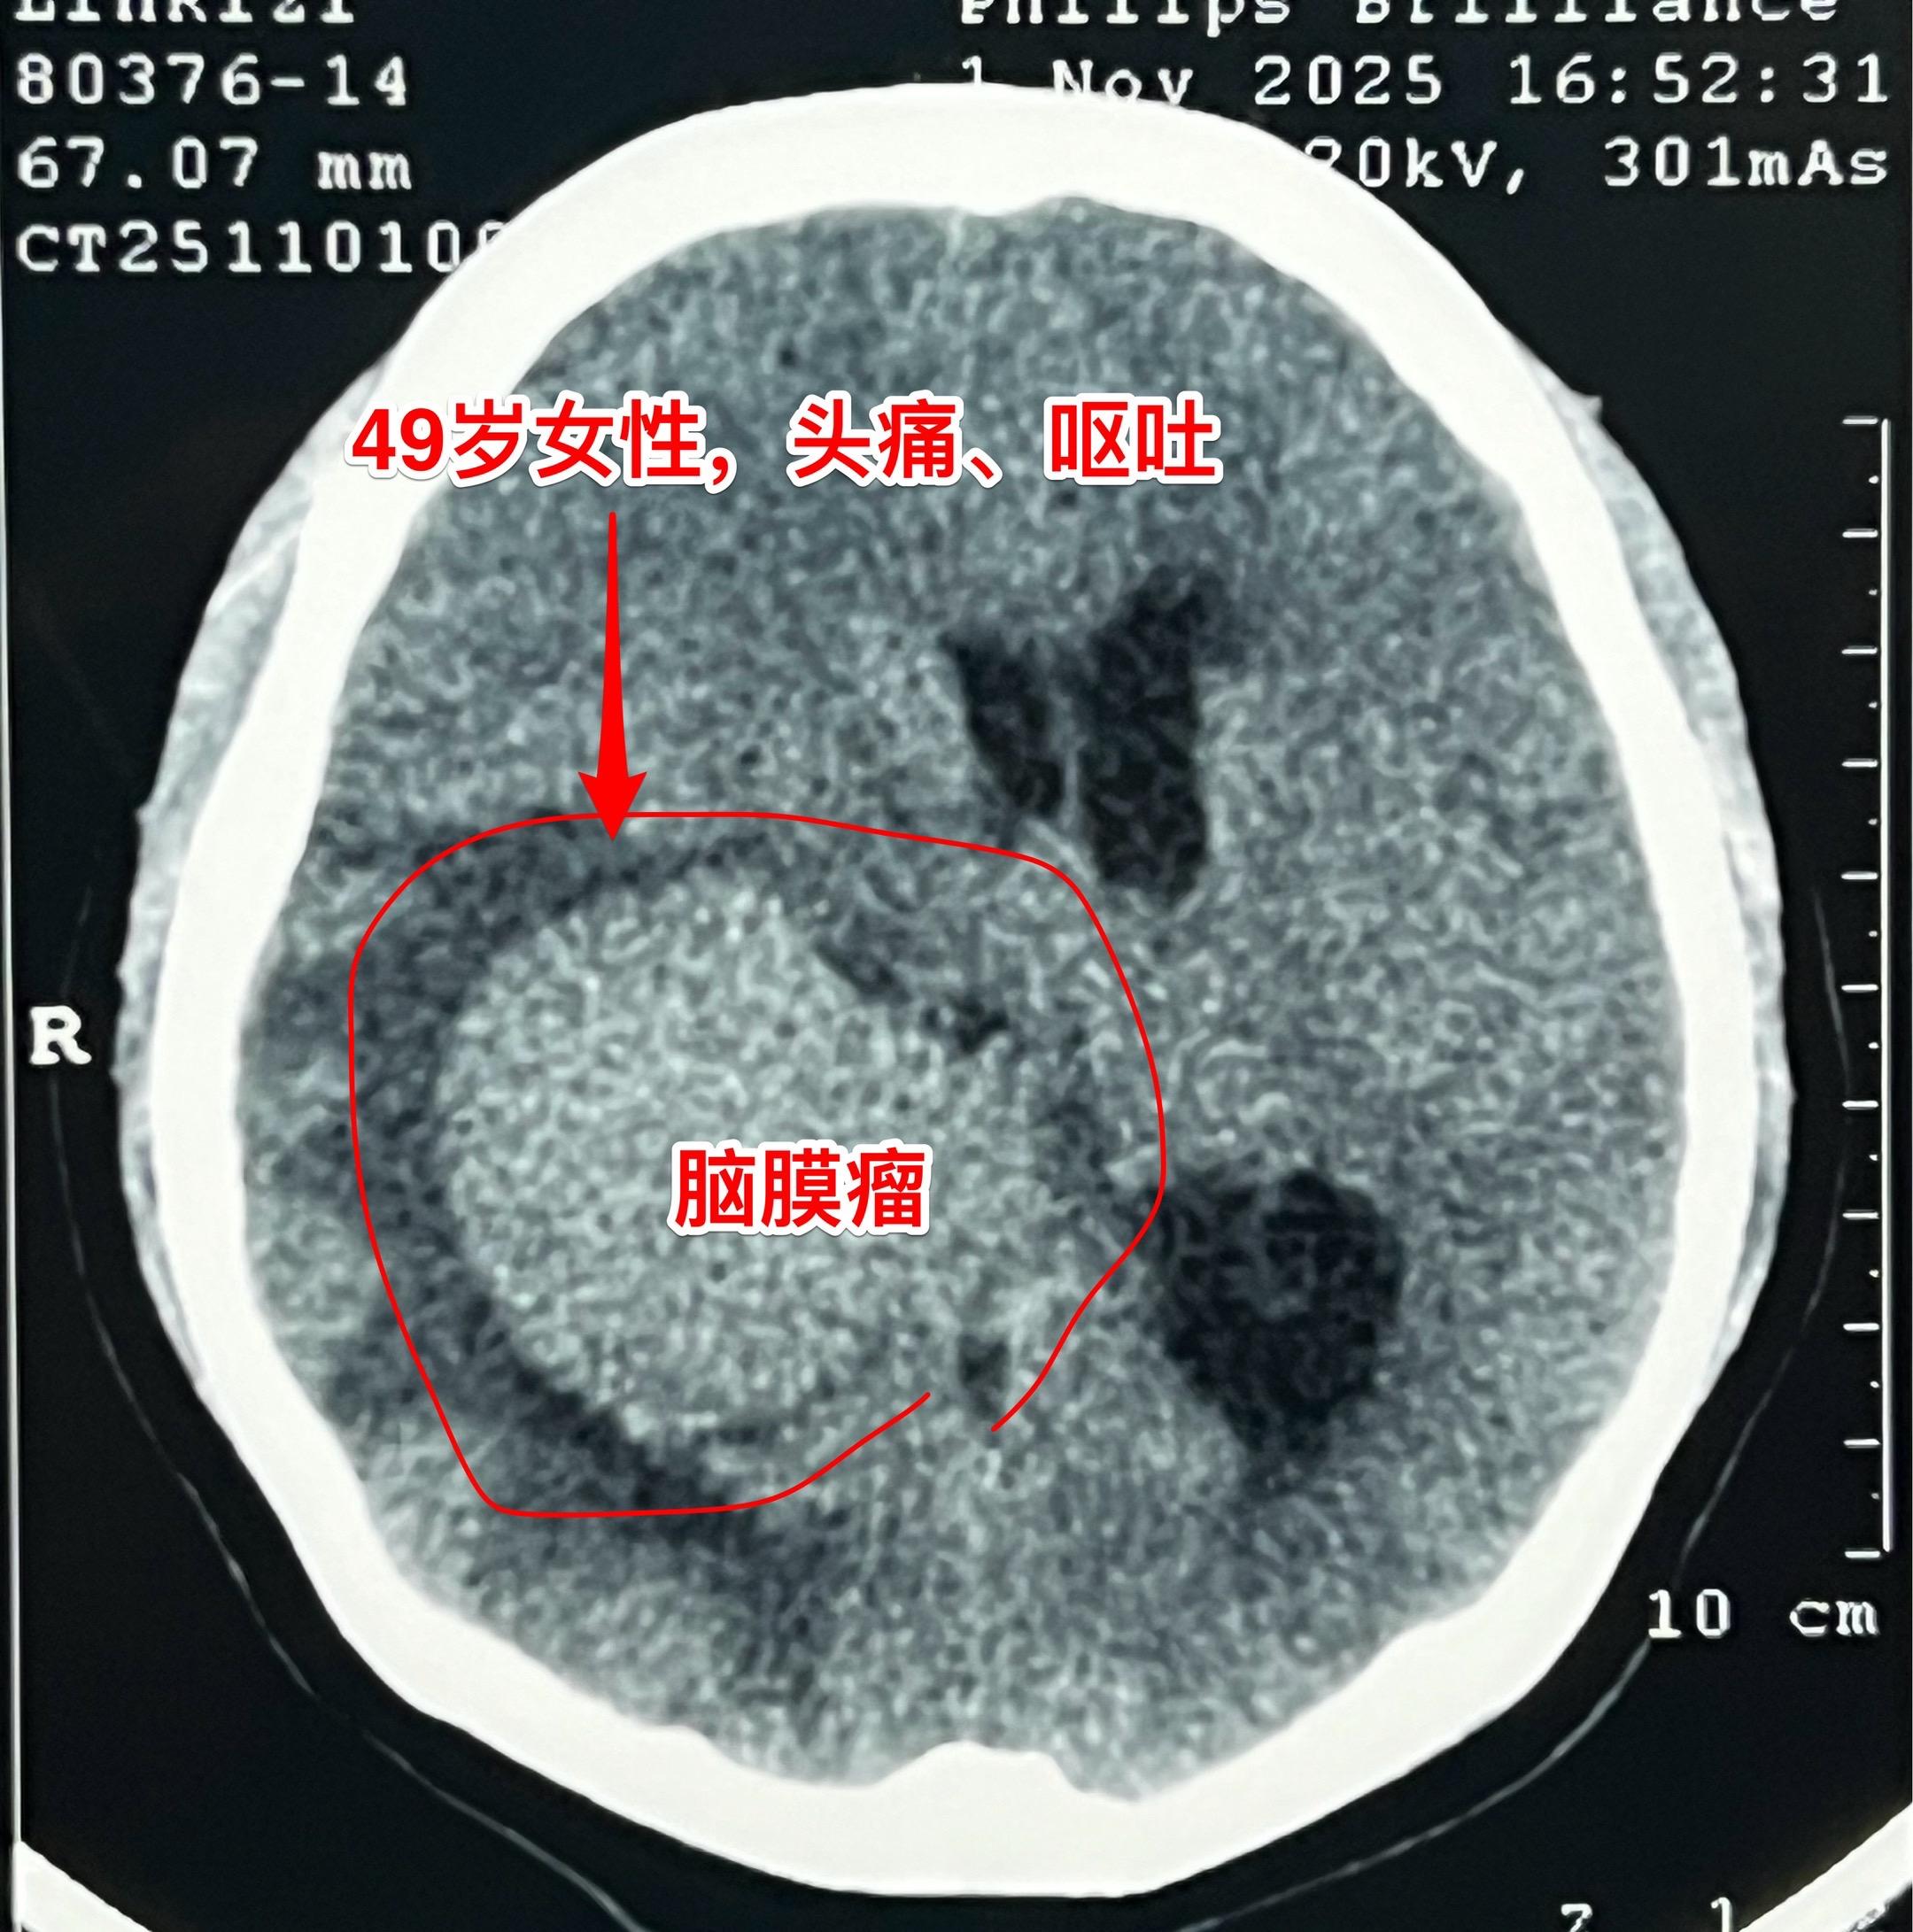

脑室内脑膜瘤也是良性肿瘤。49岁朝鲜族女性,在韩国工作,因头痛、呕吐发...